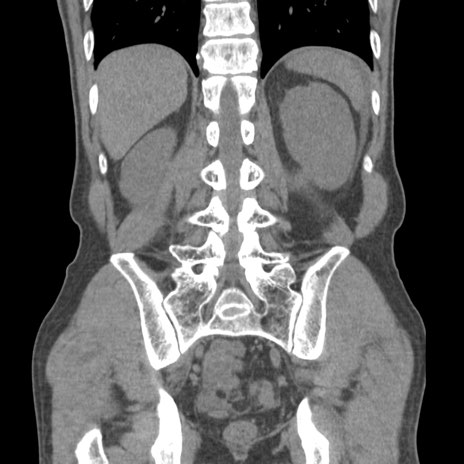

症例56 CT(冠状断像)

脂肪ウインドウ